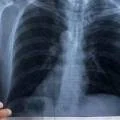

Заболеваемость туберкулезом в Мангистау осталась фактически на уровне прошлого года